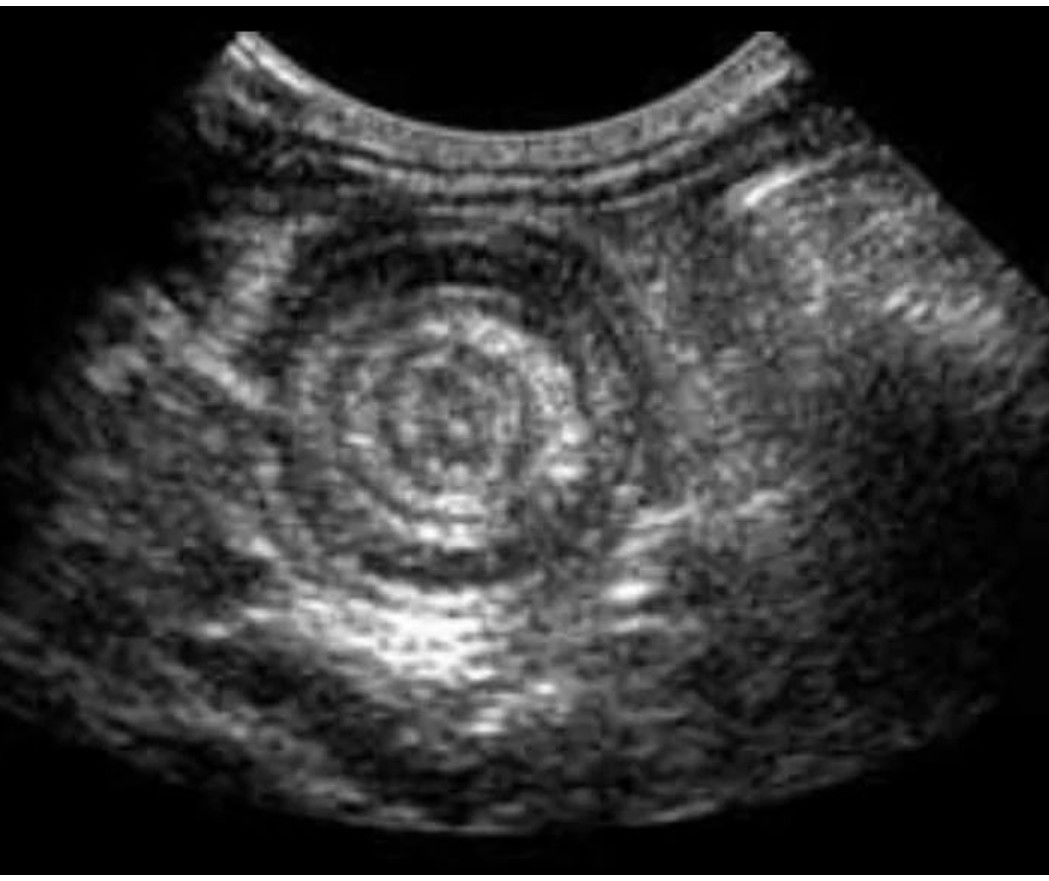

Patient presents with red currant jelly, stool. ultrasound of the abdomen showed this. Telescoping of a segment of small intestine into large intestine. Intussusception- ‘cinnamon bun sign’ or can say ‘sandwich or pseudo-kidney sign’. By: https://www.instagram.com/p/C4-zEILN-4J/?utm_source=ig_web_copy_link